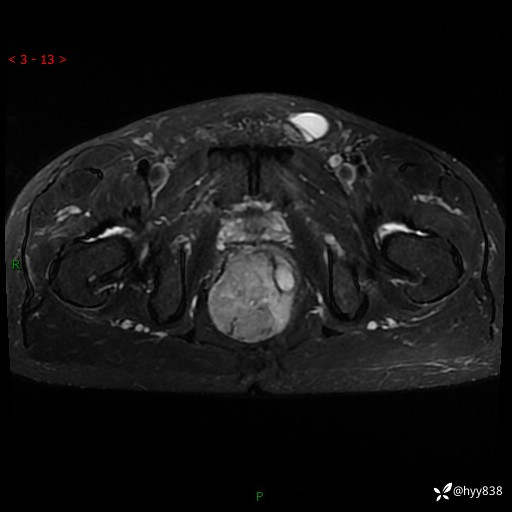

盆腔MRI平扫